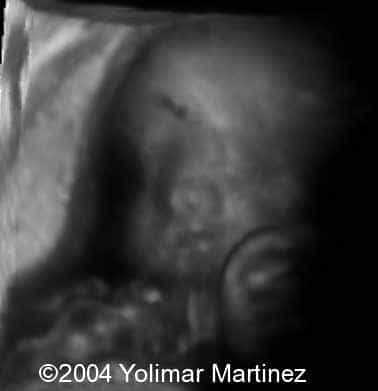

The alobar holoprosencephaly

Imagen 2